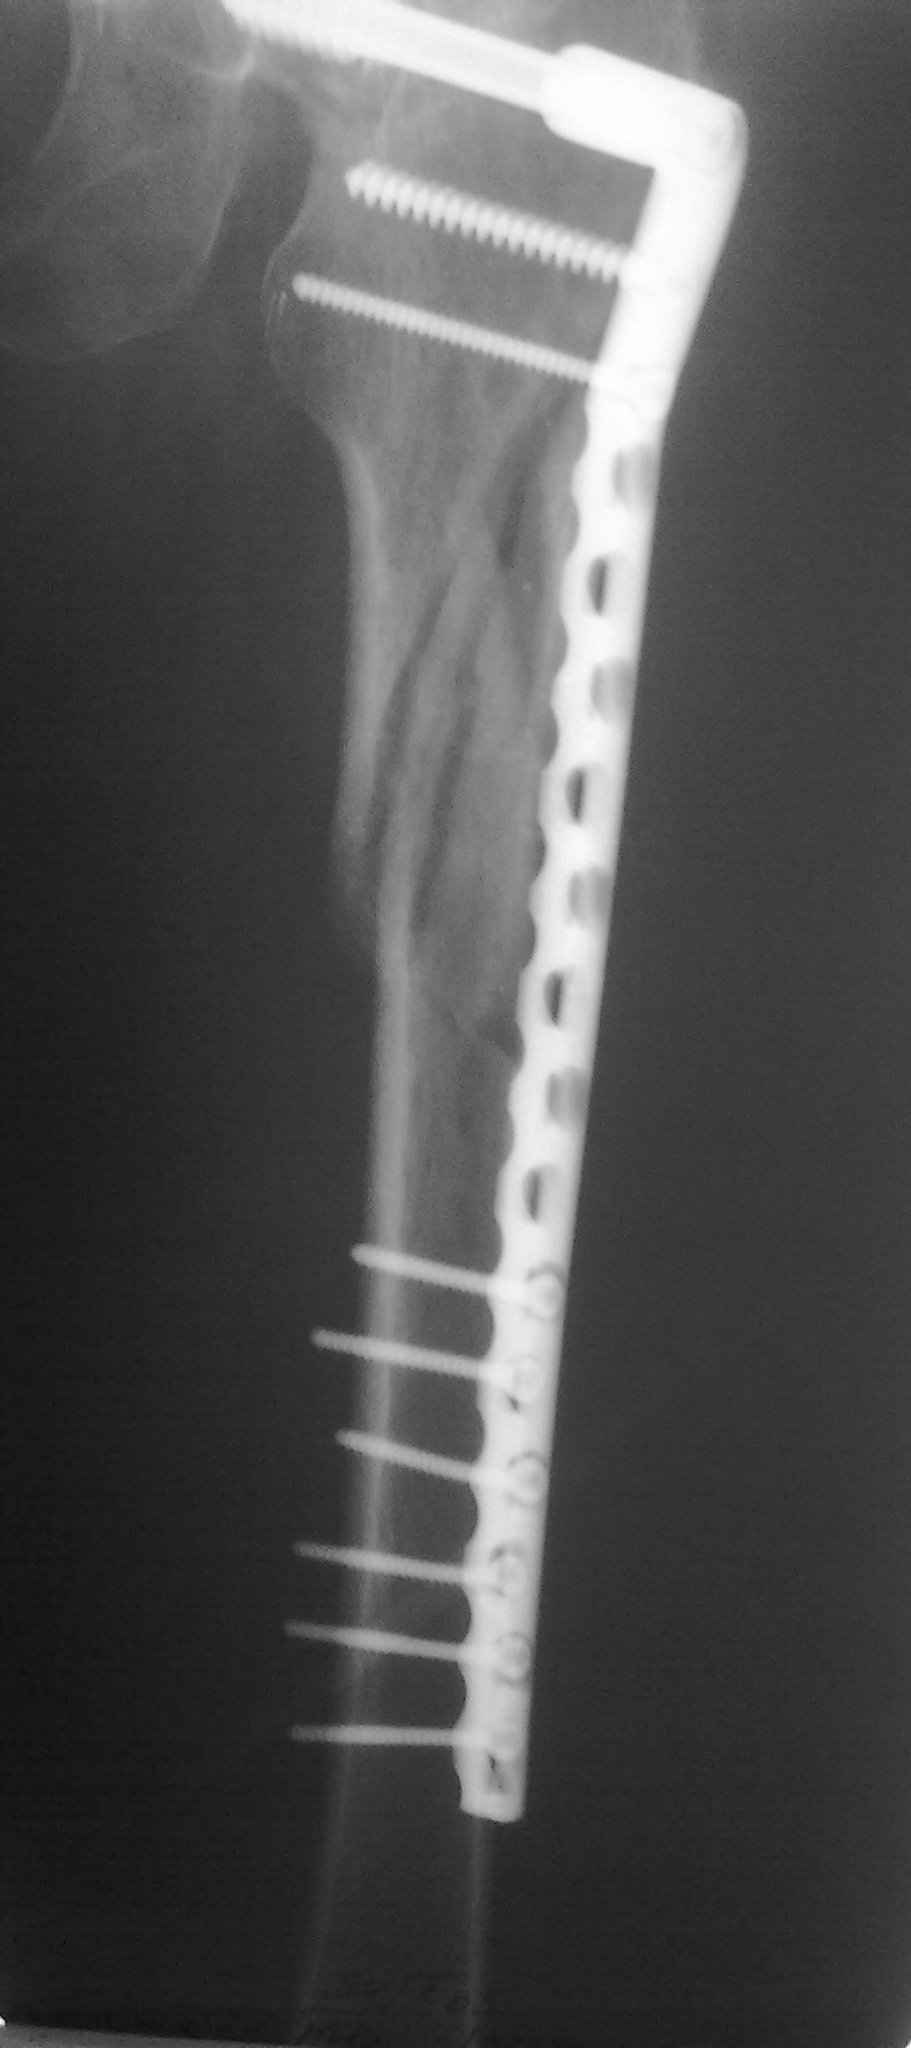

Пациент 83 года. Реконструктивный бедренный стержень Chm

Имя     : 28092009069.jpg

Тип     : image/jpeg

Размер  : 46029 байтов

Url     : http://weborto.net:8080/pipermail/ortho/attachments/20101106/4466bdf3/attachment-0004.jpg